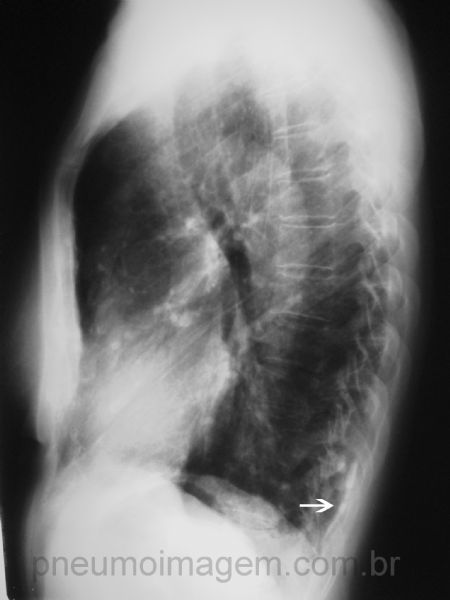

Pela incidência em perfil pode-se observar que as placas de calcificação pleural se estendem também para a região posterior (seta branca). As placas pleurais são características da exposição ao asbesto (amianto) e não necessariamente signifcam a doença asbestose.

In lateral view it can be seen that the pleural plaques also extend to the posterior region (white arrow). Pleural plaques are characteristic of exposure to asbestos and does not necessarily imply the disease asbestosis.